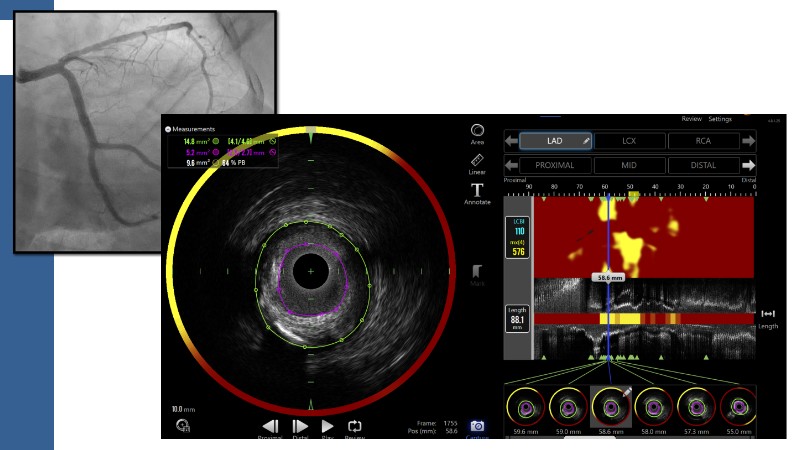

This session explores how near-infrared spectroscopy (NIRS) is redefining PCI by revealing what angiography cannot see. By identifying lipid-rich and vulnerable plaques, NIRS helps anticipate procedural risk and refine decision-making before stent implantation. The session shows how plaque composition, rather than calcium alone, can guide lesion preparation strategies, support safer stent positioning, and improve expansion. Through practical examples, it highlights how integrating NIRS with intravascular imaging and physiology moves PCI toward a more targeted, data-driven, and truly precision-based approach.

- To identify vulnerable plaques: NIRS detects lipid-rich plaques that are invisible to angiography. This allows interventionalists to anticipate complications like distal embolisation or no-reflow and adjust their approach accordingly

- To optimise lesion preparation: when NIRS reveals high lipid burden or calcific nodules, operators can choose atherectomy, intravascular lithotripsy, or specialised balloons to modify the lesion before stenting

- To improve stent placement and expansion: NIRS-IVUS guidance ensures stents are deployed in stable segments, avoiding lipid-rich or heavily calcified areas that may compromise expansion or healing